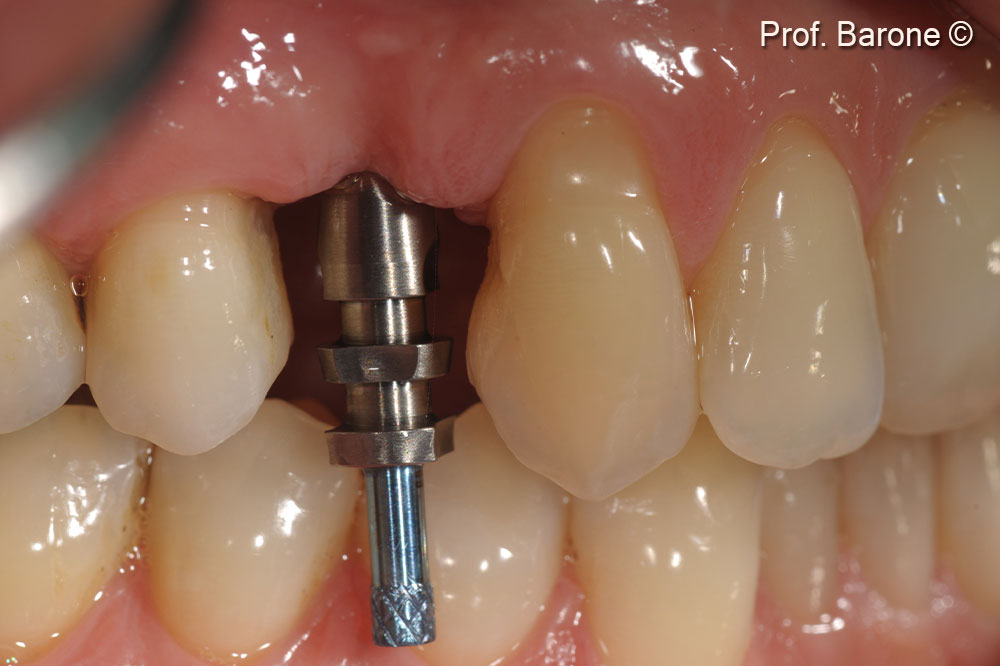

Clinical lateral view 3 months after implant placement during implant impression